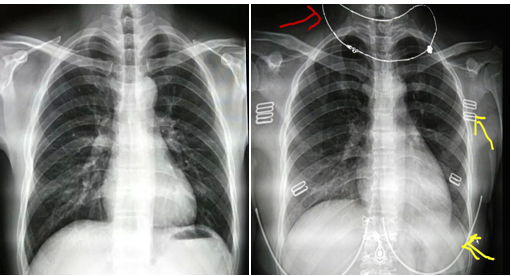

很多患者来放射科检查,肯定有过很多疑问。比如:为什么要脱胸罩,脱衣服。我们看看下面的图片,第一张是一个正常的胸部正位片。这是去除了胸罩拍的标准的片子,我们看到的肺野没有异物。双肺、心脏及骨头都显示很清楚。

图1                图2

我们看看第二张,这是没有脱胸罩照的。对比第一张,我们看到红色箭头的是戴在脖子上的项链,黄色箭头指的是胸罩的扣子和钢圈。这些体外的异物跟我们要观察的骨头和肺重叠了,如果刚好这些部位有病灶,这些体外的异物就会遮挡了病灶,导致漏诊及误诊。